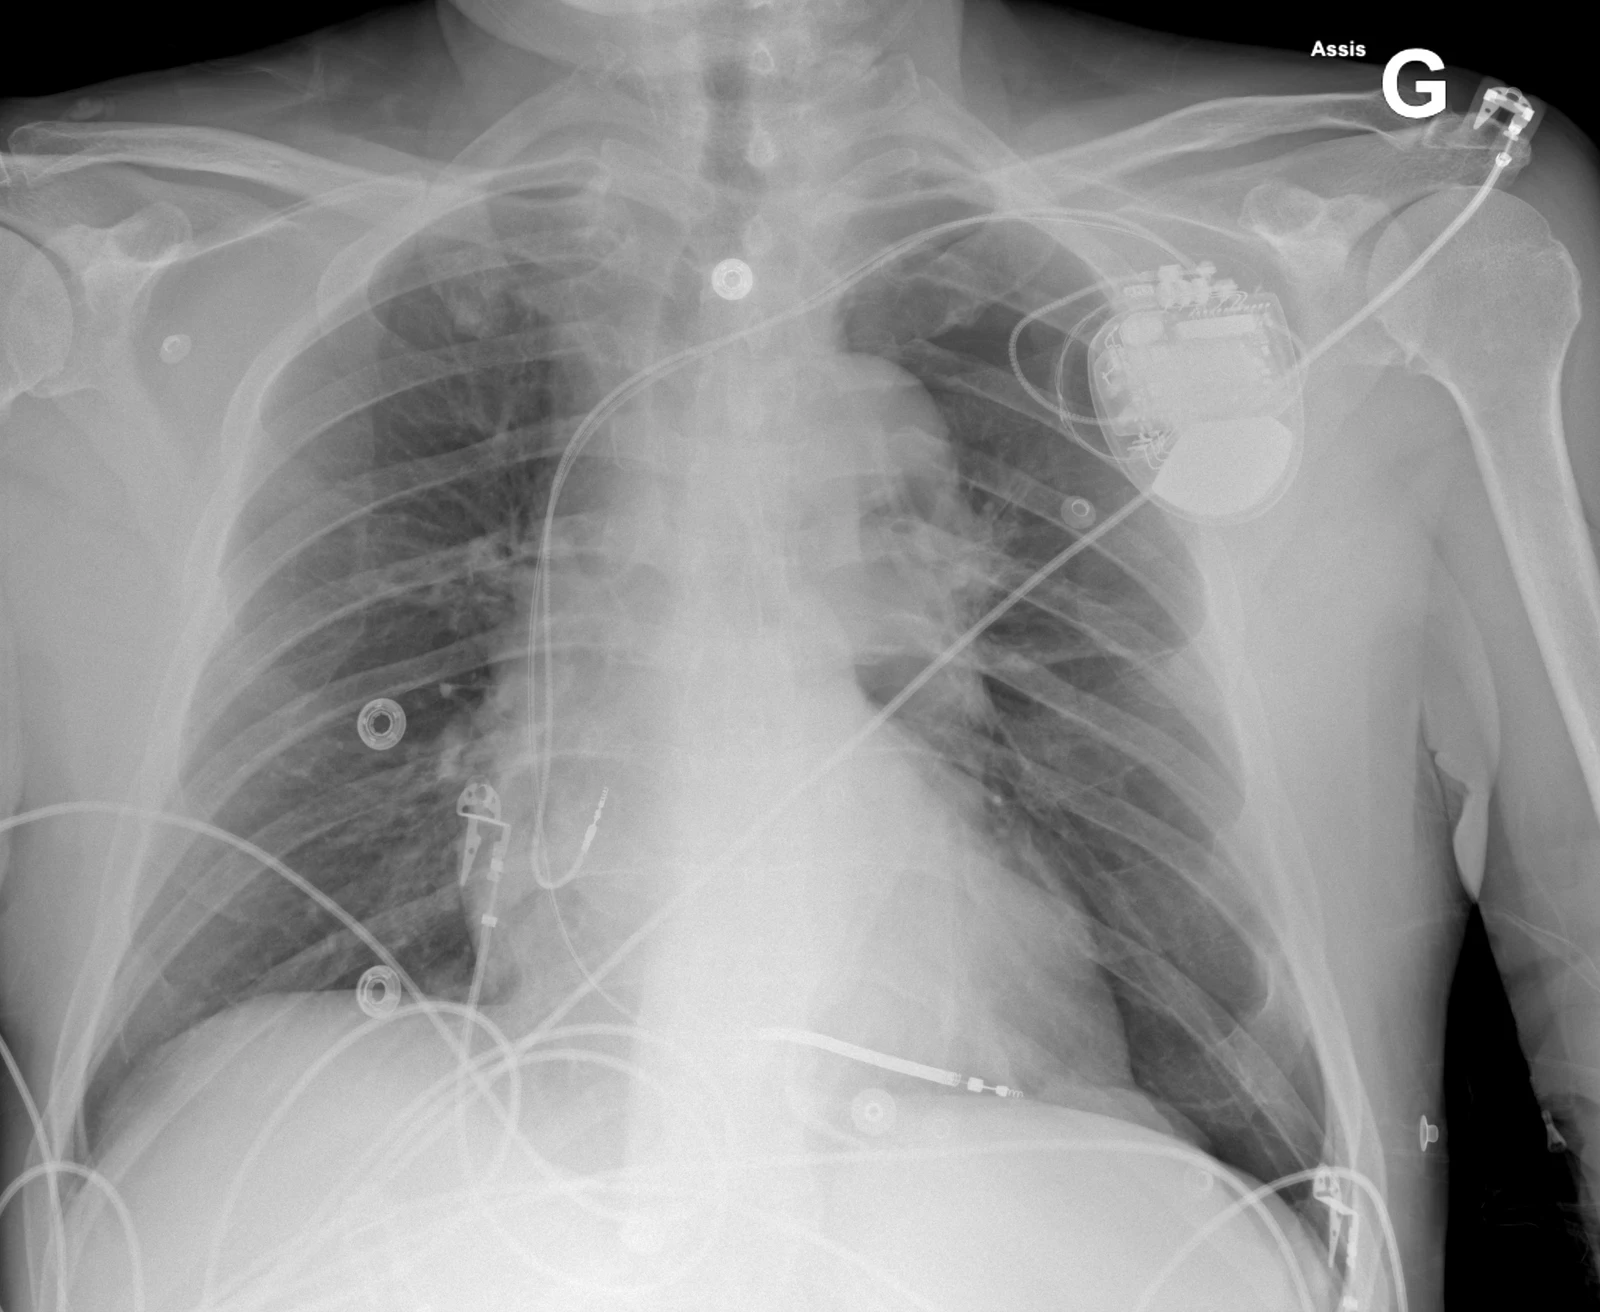

Cette radiographie du thorax a été faite chez un patient se plaignant de douleur thoracique gauche quelques heures après la pose d’un pacemaker (PM). Plusieurs complications peuvent survenir après la pose d’un PM. Le pneumothorax est une complication de l’accès vasculaire lors de l’implantation avec une fréquence de 0.9-1.3%. Les facteurs de risques sont l’âge (> 80 ans), sexe féminin, BPCO sous-jacente, PM double chambre. Le pneumothorax est une complication qui survient durant la pose du PM mais peut ne pas être reconnue immédiatement. Les patient·es se présentent avec des douleurs thoraciques respiro-dépendantes ipsilatérales au boitier du PM et une dyspnée.  Le traitement dépendra de la taille du pneumothorax et des comorbidités de la ou du patient·e. Les petits pneumothorax (< 2 cm) sont plutôt traitement conservativement. En général, un pneumothorax de > 2 cm devra être drainé.

Cette radiographie a été prise chez le même patient après la pose d’un drain thoracique à gauche et montre une disparition radiologique du pneumothorax.

A noter qu’on utilisera si possible un drain de petit calibre (≤ 14 Fr). La voie antérieure (ligne médioclaviculaire) utilisée pour exsuffler un pneumothorax en urgence peu également être utilisée pour poser un drain (de préférence de petit calibre), offrant l’avantage de poser le drain à l’endroit où se trouve l’air. En cas de pose de PM récente, ce dernier peut gêner l’abord antérieur.